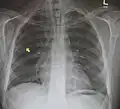

Pneumomediastinum is uncommon and occurs when air leaks into the mediastinum. The diagnosis can be confirmed via chest X-ray showing a radiolucent outline around the heart and mediastinum or via CT scanning of the thorax.

Pneumomediastinum and right sided pneumothorax post first rib fracture in a mountain biking accident. -